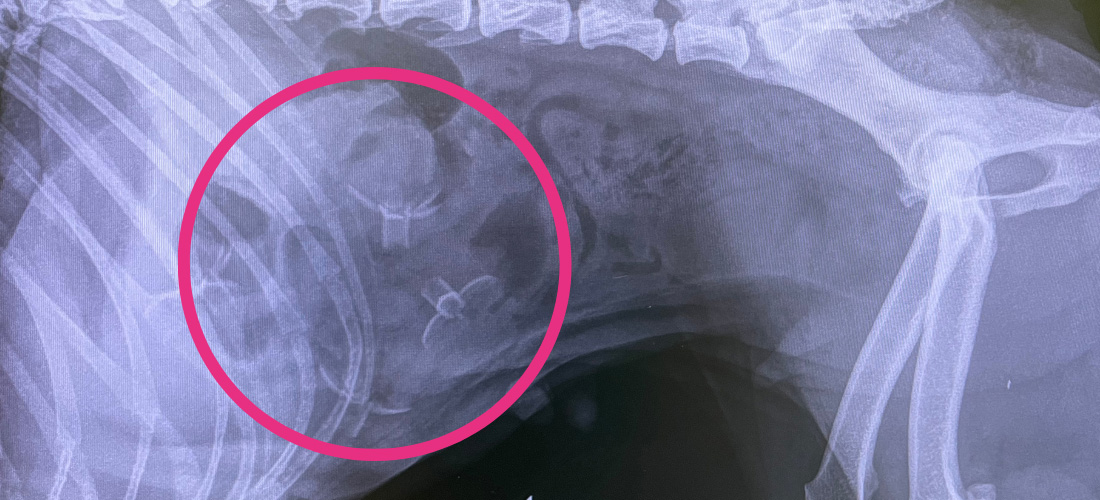

PDSA Vet, Kirstin Sunderland, said: “We were extremely concerned that Paris might have a blockage in her guts, so we arranged for further tests as soon as possible. X-rays showed an obvious linear foreign body.

“Paris was taken to theatre straightaway as she needed complex surgery to remove the foreign material; it extended from her stomach to her jejunum and ileum (the middle and the last part of the small intestine). The object appeared to be a sequence of five to six plastic objects resembling flowers that were connected via string.”